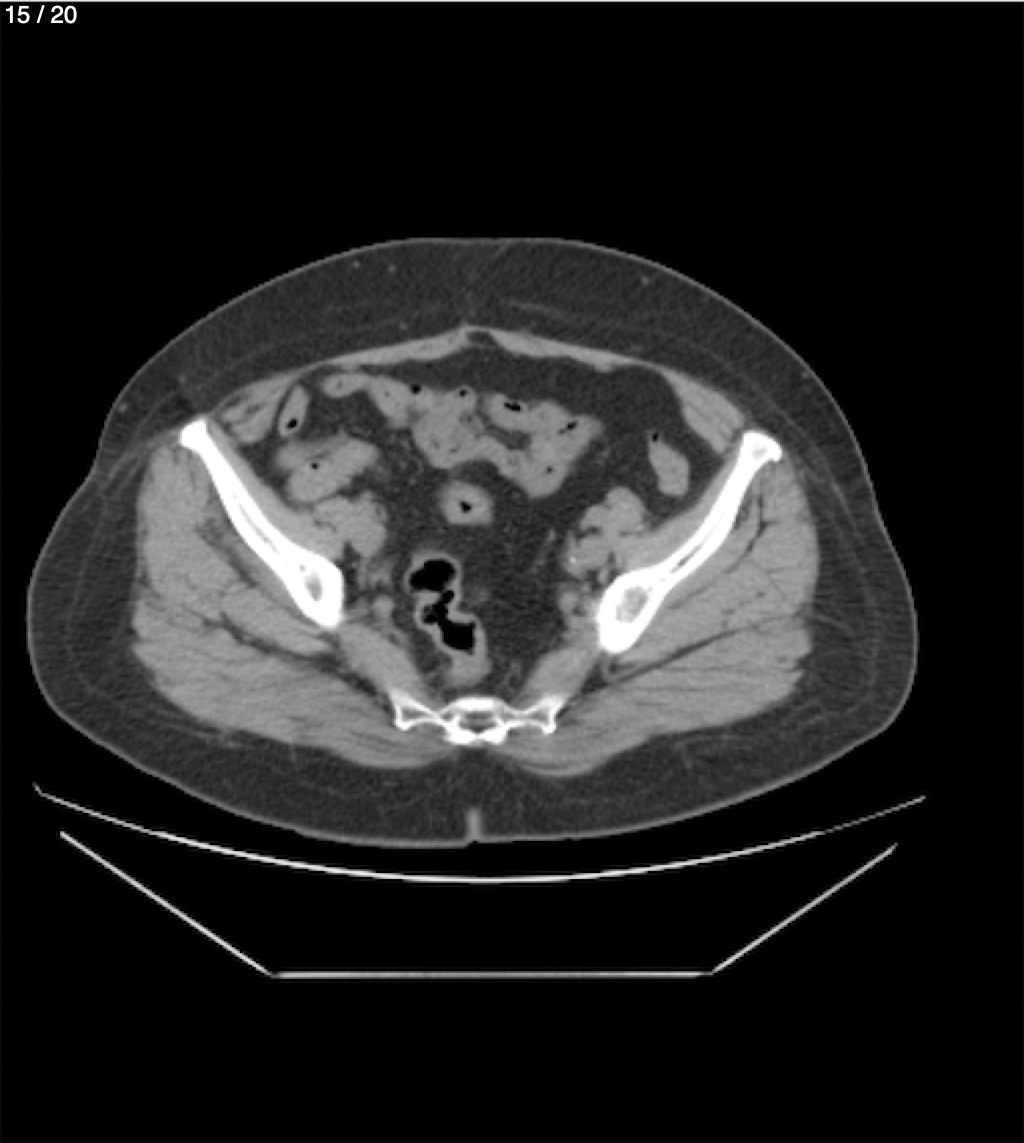

Maria Enrique Giron Dominguez63A - T.C Abdomen Simple